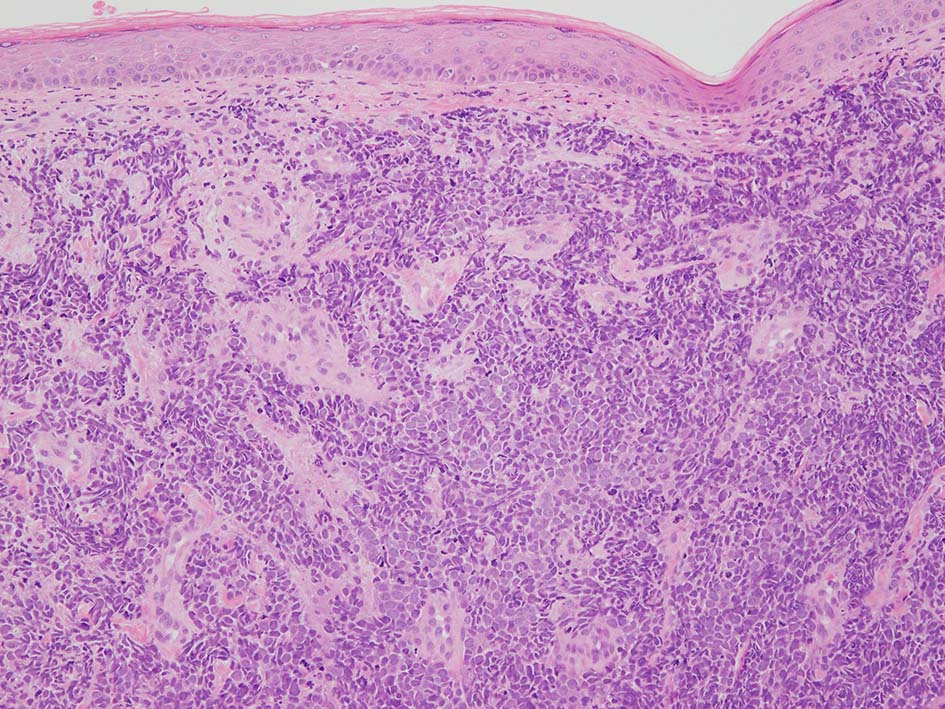

皮膚原発性Merkel細胞癌は 通常真皮を病変首座に増殖し, しばしば脂肪織まで浸潤する.

表皮とは連続性がなくGrenz zoneがみられるのが特徴であるが, 病理所見は多様であり, ときに表皮向性を示す症例やpagetoid patternを呈する症例もある.

下肢皮膚の赤色隆起性病変. 頂部の潰瘍部分より生検をおこなう.

loupe像 HE